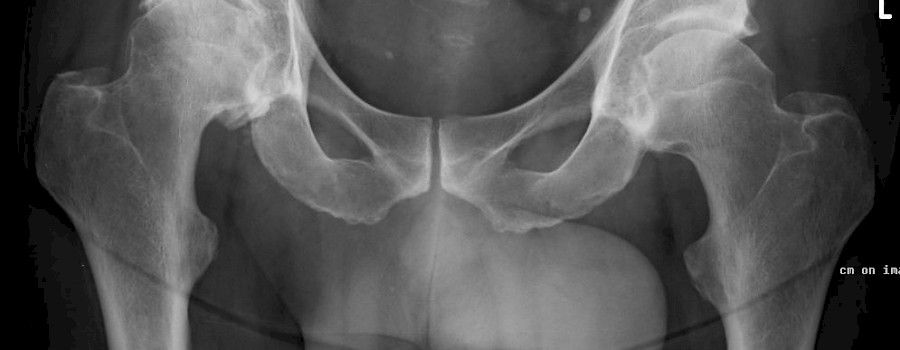

Was ist auf unserem heutigen ominösen Röntgenbild abgebildet?